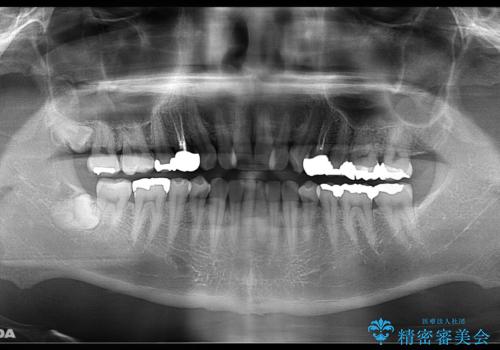

- お口の中にある銀歯を無くしたいとご相談にいらした方です。

適合の良いセラミックにてやり替えを行いました。

元々噛む力が強く、日常的に歯ぎしりもされるとの事でしたので、歯が割れてしまうリスクを軽減させるため、歯全体を覆うクラウンをメインに補綴治療を行いました。

適合不良の補綴物は二次的な虫歯発生のリスクが高まります。

自費診療で用いられる材料は保険適応の材料に比べて、より精密で適合の良い被せ物作ることができるため、長期的な虫歯のリスクを大幅に減らすことが可能です。